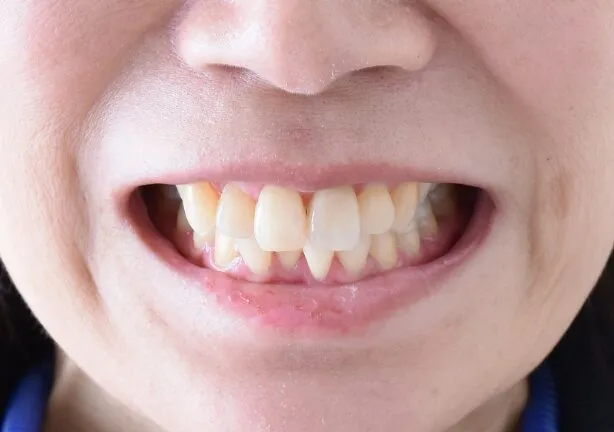

case2

Before

治療内容 | 口腔内診査〜カウンセリング 歯周初期治療 仮歯にて噛む位置の再設定 インプラント埋入 仮歯にてインプラントを含めた噛む位置の決定 最終的な被せ物(ジルコニア)の型取り〜装着 |

---|---|

治療期間 | 1年半 |

治療回数 | 40回 |

リスク | リーニングにこない場合噛み合わせの確認ができないため装着していった人工物が割れてしまう可能性があるため、今後のメンテナンスが必須となる |

費用(税込) | 約¥2,860,000 |